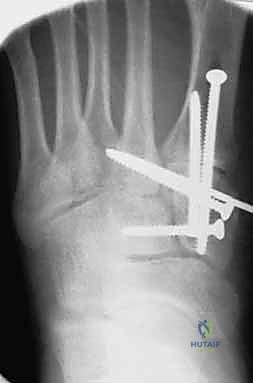

1. الرد المفتوح والتثبيت الداخلي (ORIF - Open Reduction and Internal Fixation)

هذا هو الإجراء الكلاسيكي والأكثر شيوعاً. يهدف إلى إعادة العظام إلى مكانها الطبيعي (الرد) وتثبيتها باستخدام معدات طبية (مسامير، شرائح، أو أسلاك) حتى تلتئم الأربطة والعظام.

4. التثبيت (Fixation): يتم تثبيت العظام باستخدام مسامير معدنية خاصة (Solid or Cannulated Screws) تعبر المفاصل لتثبيتها بإحكام. في بعض الحالات، يتم استخدام شرائح معدنية صغيرة للحفاظ على الاستقرار.

5. مسمار ليزفرانك: الخطوة الأهم هي وضع "مسمار ليزفرانك" (Lisfranc Screw) الذي يمر من العظم المسماري الإنسي إلى قاعدة المشط الثاني، لتعويض وظيفة الرباط الممزق.